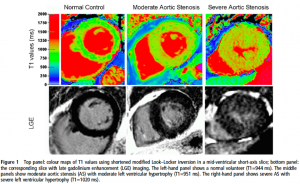

Magnetic Resonance Imaging (MRI)はSHD領域において弁膜症重症度評価や心機能、心臓繊維化などの評価に使用される。MRIの最も大きな利点は非侵襲的に正確な形態学的評価が可能であり、同時に組織学的評価ができることである。

空間分解能については1.2-1.5 mm程度であり、CTには劣るものの詳細な評価が可能であり、TAVIにおける大動脈評価に関してはCTでの評価との良好な相関が報告されている(9,10)。また、エコーでの評価が困難な右室における容量評価のreference methodとして推奨されている(3,11)。また、SHD領域におけるT1 mappingやガドリニウム遅延造影を用いた心筋繊維化の評価は近年数多くの報告がなされており、注目を集めている領域となっている(12,13)。

(文献13より引用: AS患者におけるT1 mappingとLGE)

(文献13より引用: AS患者におけるT1 mappingとLGE)

これらの利点をみるとMRIは万能であると思われるかもしれないが、MRIはCTと比較し撮像時間が長く、被験者を選ぶmodalityである。閉所恐怖症など姿勢保持や呼吸停止指示が困難な被験者における画像の取得は困難である。また、ペースメーカーや植え込み型除細動器などの禁忌が存在することも限界の一つである。コスト、汎用性についても現時点では他のmodalityに及ばないと考えられる。